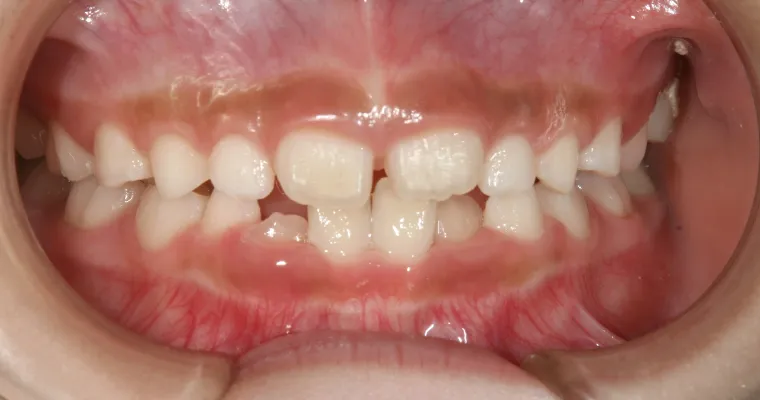

正面観

BEFORE

AFTER

| 主訴 | 歯並びが悪い 乳歯と永久歯が重なっている 歯がまっすぐはえてこない |

|---|---|

| 治療期間 | 6-7ヶ月 |

| 治療費 | 440,000円(税込) ※調整、器具、治療後にお渡しするEFLine(矯正後の後戻りを防ぐ器具)も全て込みでの金額となっております。 |

| 治療内容 | 拡大床矯正 EF Lineで筋機能療法 |